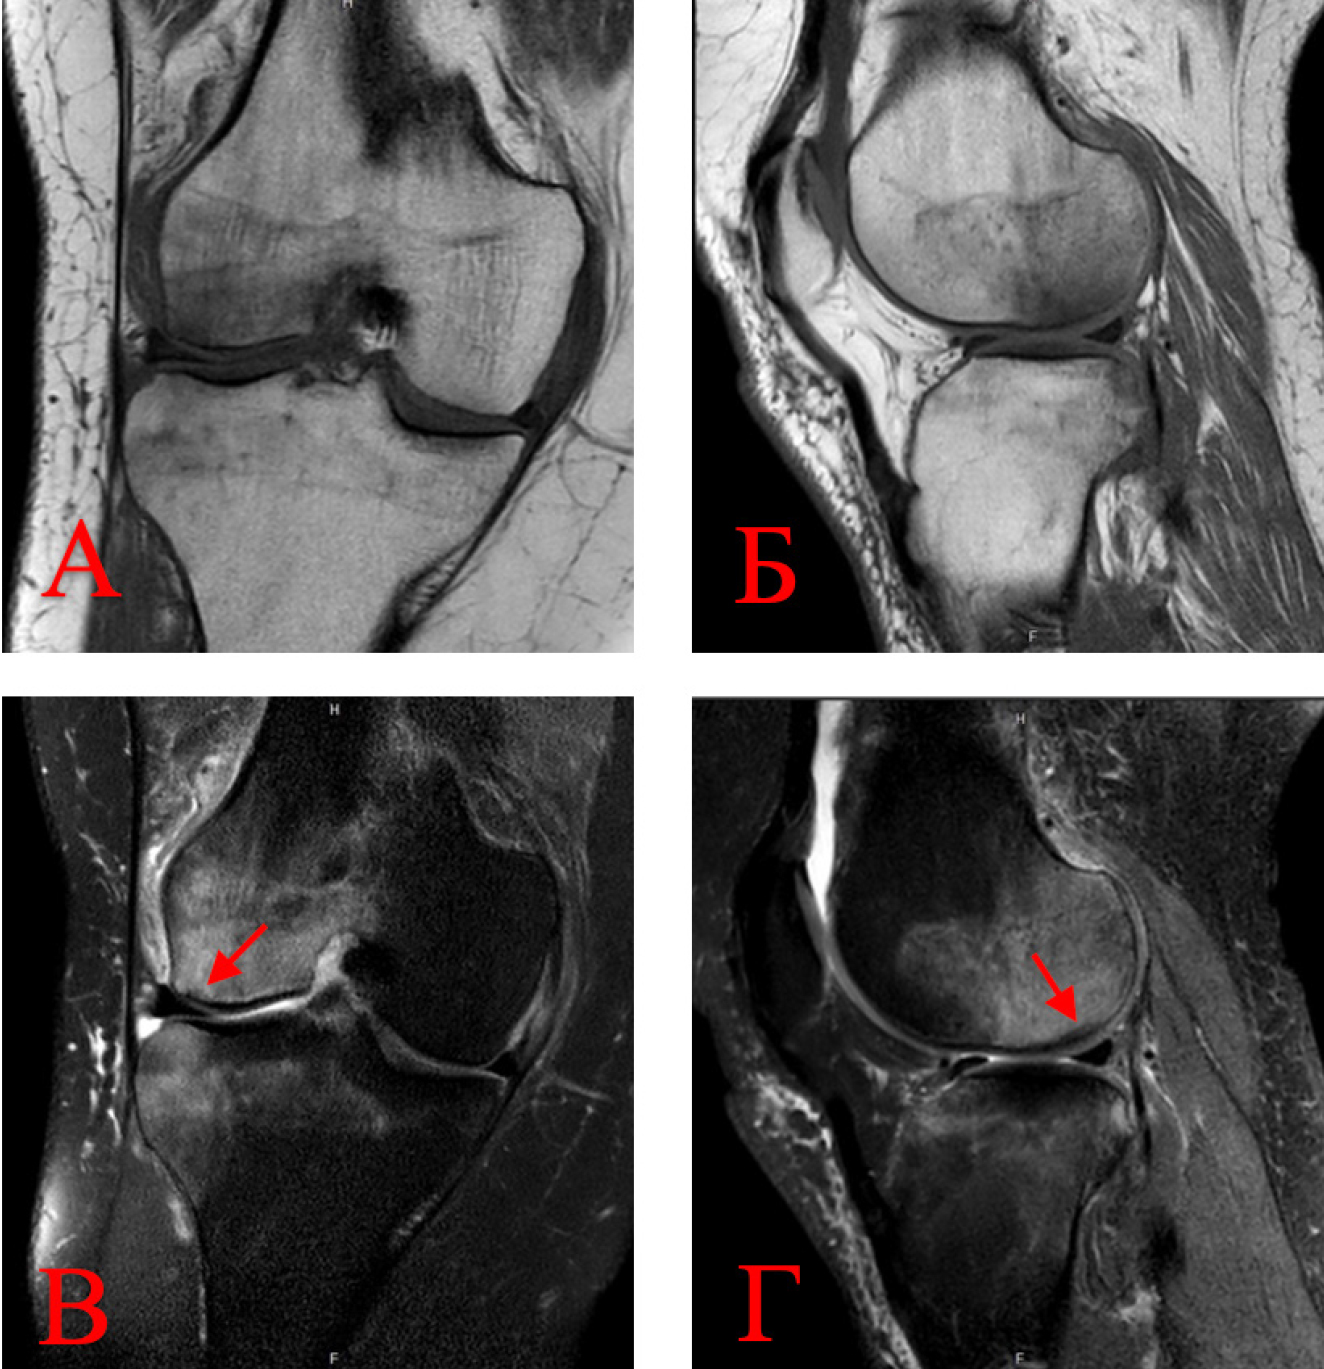

Объективным показателем регресса болевого синдрома и нормализации клеточного метаболизма субхондральной кости в результате устранения ишемии костного мозга являлось значительное сокращение площади или вовсе исчезновение зон трабекулярного отека костного мозга, что подтверждалось уменьшением линейных размеров гиперинтенсивных участков по данным МРТ. Зона некротического очага по своим линейным характеристикам осталась прежней (рис. 5).

Рис. 5. Регресс признаков ишемии и трабекулярного отека костного мозга: А, Б – прямая и боковая проекции на Т2-взвешенных изображениях